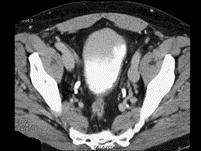

问题 男,55岁,血尿半月余,请根据其影像,判断其最可能的诊断 ( )

选项 A、膀胱憩室伴感染 B、慢性膀胱炎 C、膀胱癌 D、膀胱憩室 E、膀胱结石

答案 C